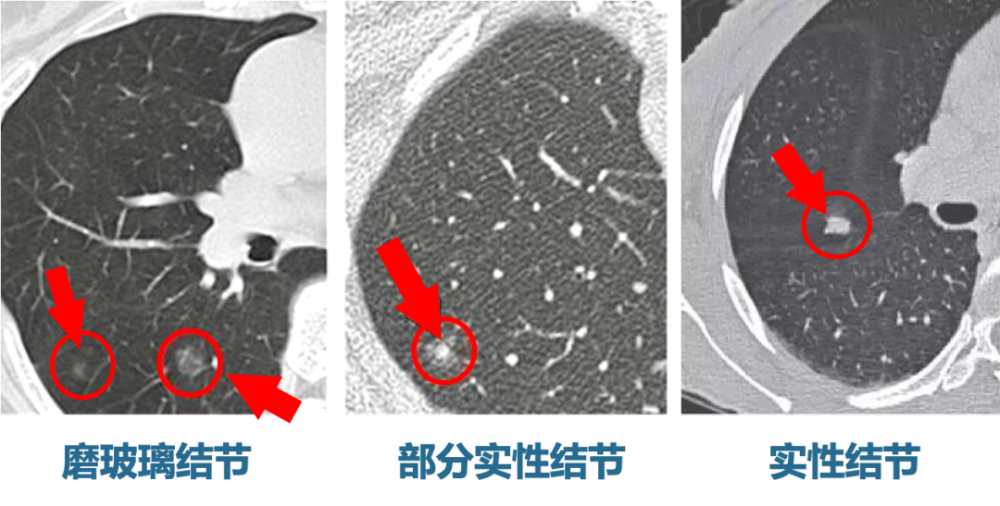

好运模式开启多位专家判断高危的7mm磨玻璃肺结节变成斑片影